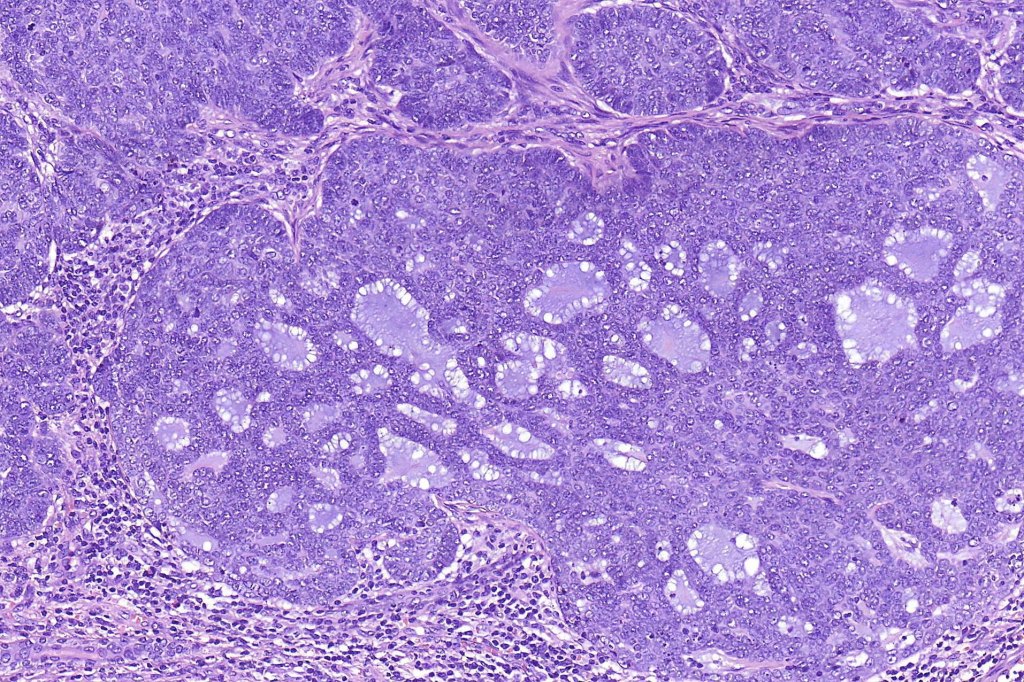

•Cribriform nests, tubules , cords & solid nodules

•Small ducts and pseudocysts